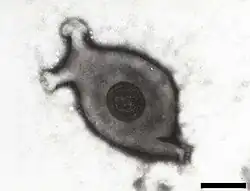

| Electron micrograph of Mycoplasma gallisepticum, scale bar 140 nm | |